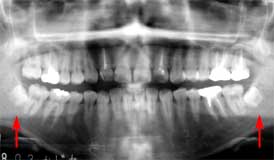

Topic No.87

初診時 パノラマ 「8 拡大図 抜去 術式

下顎左側に埋伏した智歯が認められる

レントゲンで見る以上に骨が歯冠部分を覆っている 周囲骨削除の上、歯冠カット

主訴は、|12の腫脹。

主訴の|12は、歯根中央部の崩壊に伴う炎症が存在した。それ以外にも6|の 根尖病巣による腫脹が認められたが、清掃状態は比較的良好で、「8の埋伏を認めるも 臨床症状はないように思われた。

上顎の治療を終了後メインテナンスに移行して約1年経過したころより、「8部の疼痛を訴えるよ うになった。

「7遠心の歯肉腫脹を起こすに至って、切開・排膿を試みると同時に探針で「8の埋伏状態を探った が、歯冠を触知することが難しくほとんど"完全埋伏歯"に近いことが疑われた。 ほとんど"完全埋伏歯"であることから、当初は、「7遠心根に歯石が沈着して起こした炎症を 疑ってしばらく経過を観察することとしたが、炎症は軽快することなく再び排膿を伴う腫脹を 起こしたことを契機として抜歯を決断。

歯冠のほんの一部が露出した埋伏歯であることから、周囲骨を大きく削合して、通例に従って 歯冠カットのうえ抜歯を行った。術後の経過は良好。

歯肉の上に顔を出した埋伏歯はほとんど抜歯の対象となるが、骨内に完全に埋伏した 智歯は炎症を起こさない限り抜歯の対象となることは少ない。しかし、わずかといえども 歯肉の隙間を介して口腔内と交通した場合には炎症を起こすことも決して稀なことではない。 ひとたび炎症を起こすようになった智歯はいつか抜歯しなくてはならない運命にあるといえる。

本症例の場合は、周囲骨の削合に結構時間を要したが、幸いにも歯根形態が単純であった ので比較的容易な症例であった。

上顎の埋伏智歯ほどではありませんが、これもあまりかかわりたくない症例です。